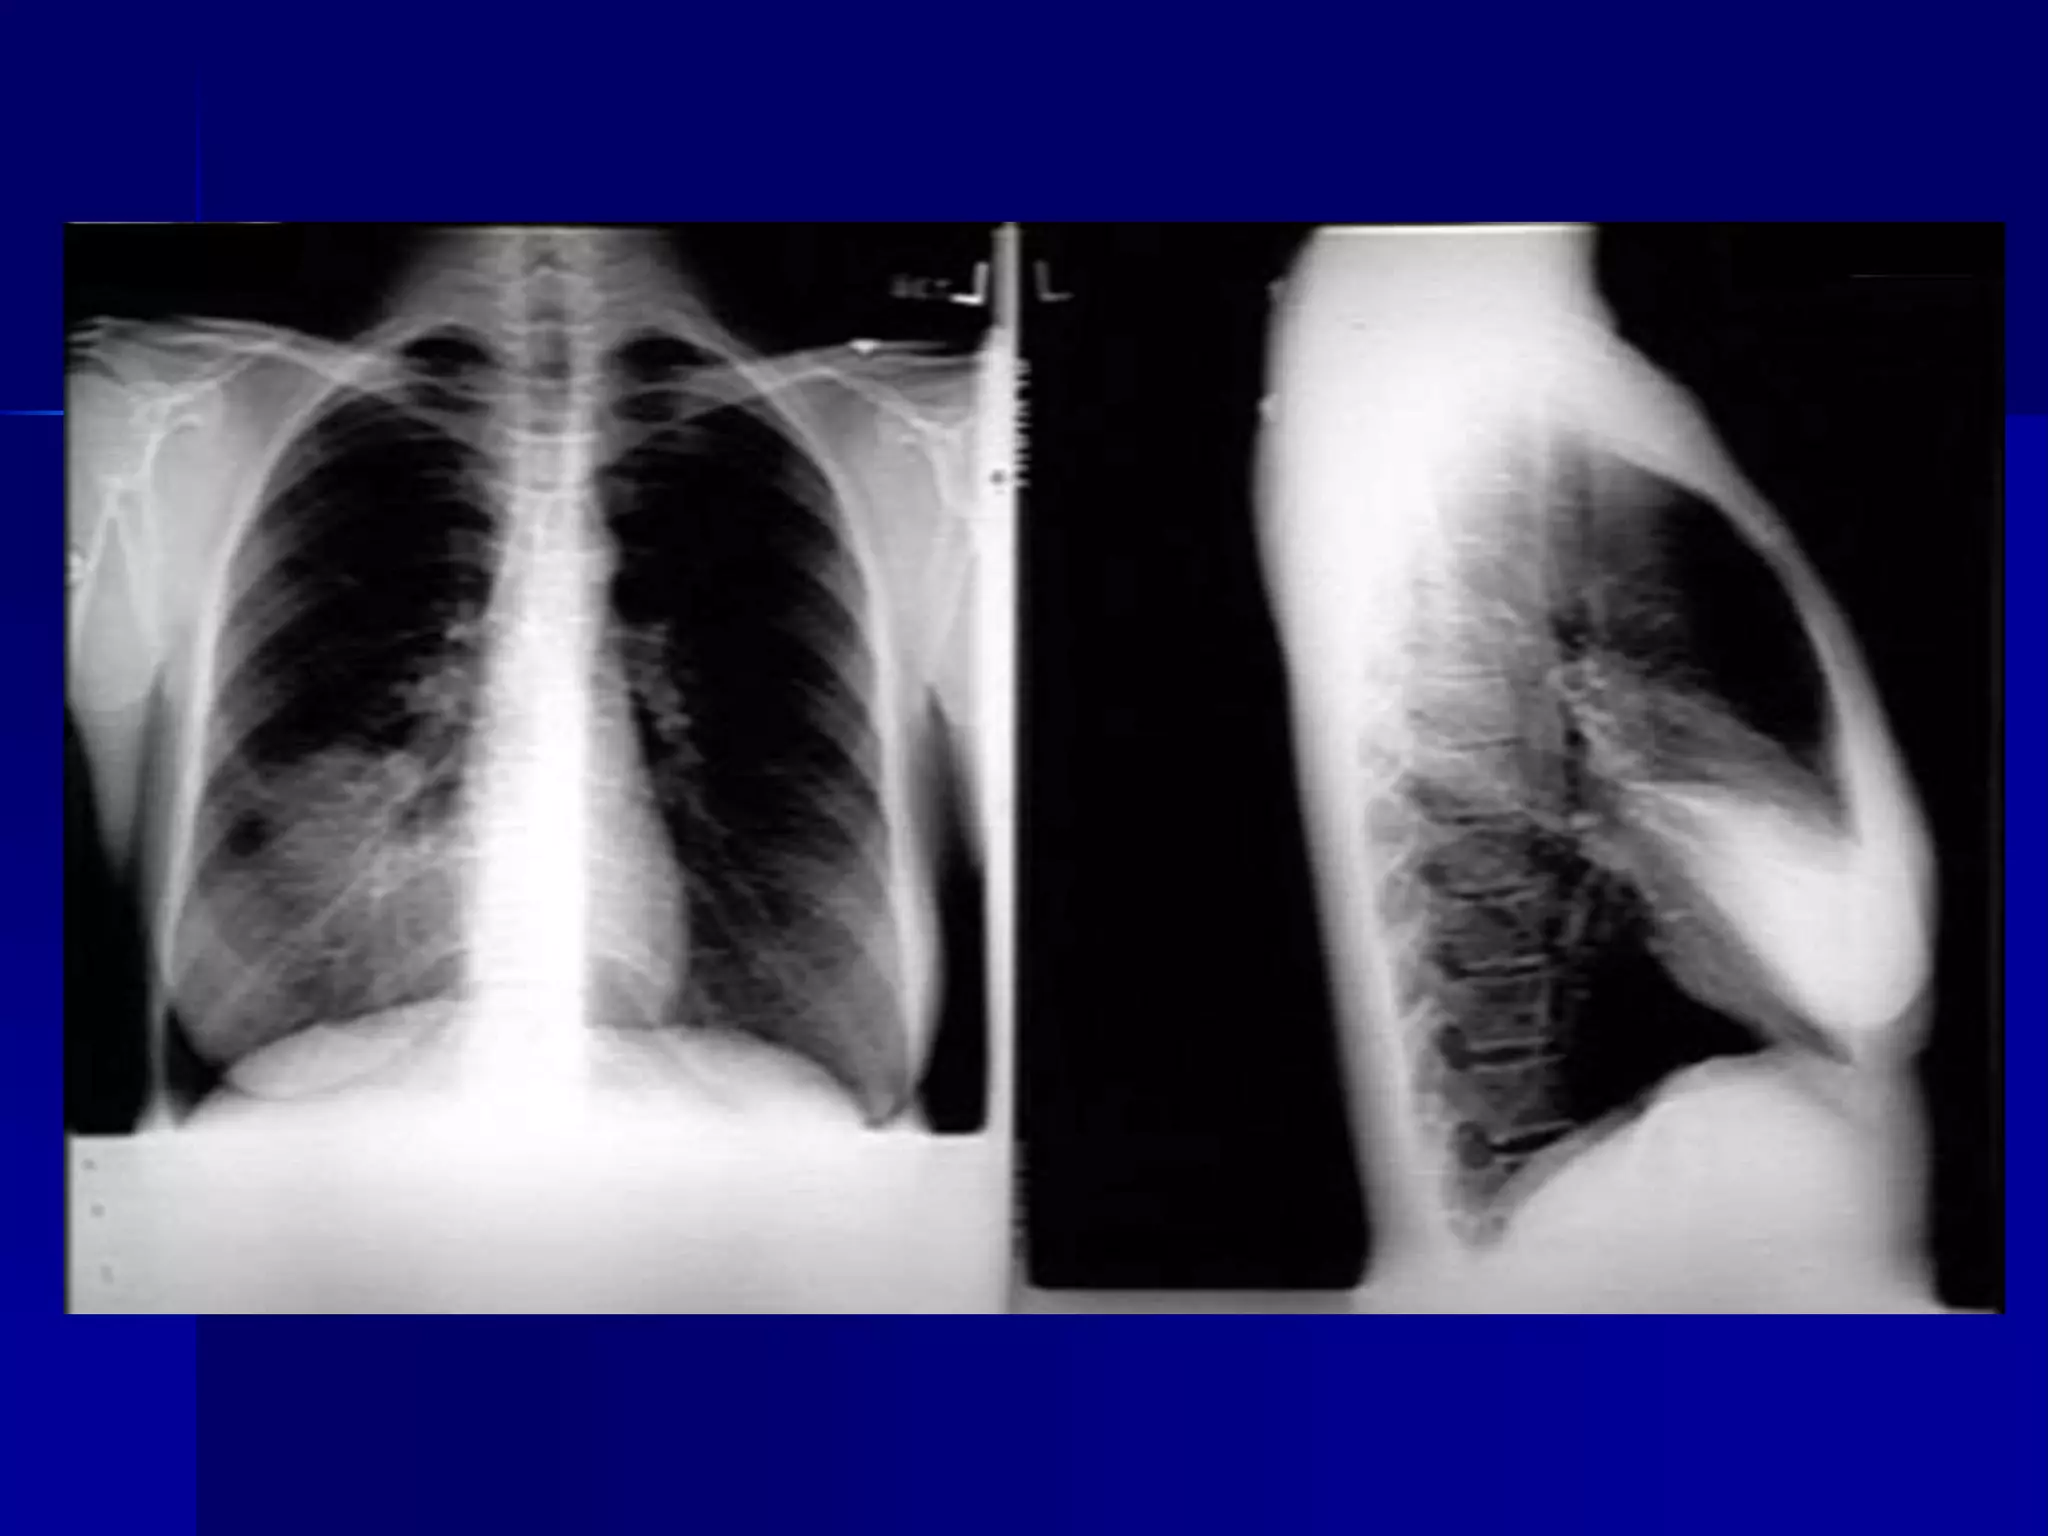

 Bronchiectasis

 Multiple bilateral basal air fluid levels

 Pleural Effusion

 Rheumatoid Arthritis

 Chest lateral and hand x-rays.